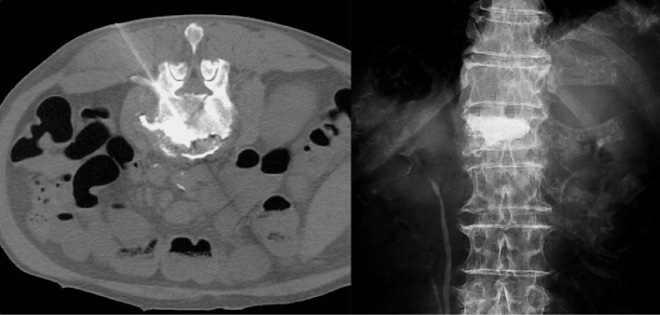

[方 法] 腹腔神経叢ブロックでは,大動脈前面の腹腔神経叢を遮断し,内臓神経ブロックでは横隔膜脚,椎体前面,大動脈で囲まれるコンパートメント(retrocrural space)内で内臓神経を遮断する(図2)。X 線透視,CT ガイドまたは超音波内視鏡下で行う。

図2 経椎間板アプローチ腹腔神経叢ブロック

大動脈周囲に造影剤の広がりが認められる。